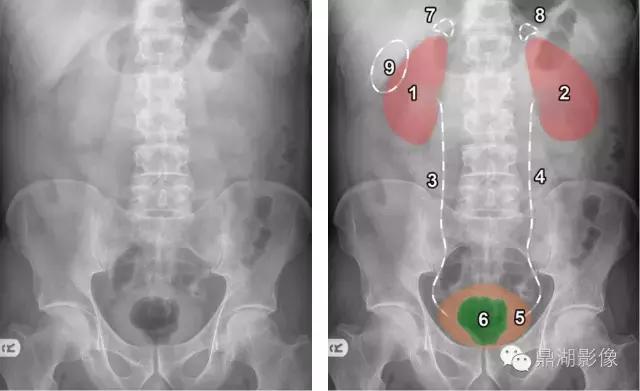

1.右肾 2.左肾 3所标示的白色线条为右侧输尿管的位置,同理4是左侧输尿管的位置,5.膀胱 6.直肠气体影 7.右侧肾上腺的位置 8.左侧肾上腺的位置 9.胆囊的位置

,胆囊的位置非常多变。它可以出现在右上象限的任何地方。最常见的位置就是上图的位置。